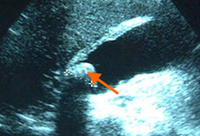

Ultrasound of acute cholecystitis and presence of gallstones: the arrow points to a gallstone in the fundus of the gallbladder with its echogenic shadow below

Courtesy of Charles Bellows and W. Scott Helton; used with permission